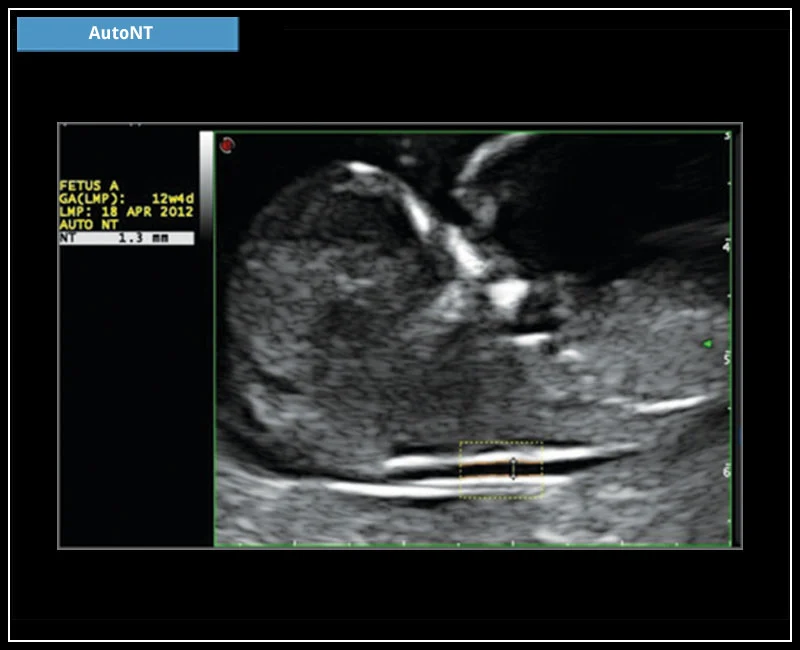

MyLab™9 Platform - HD Zoom on fetus profile with AutoNT measurement

MyLab™9 Platform - HD Zoom on fetus profile with AutoNT measurement

MyLab™X5 - AutoNT

MyLab™X5 - AutoNT

MyLab™X6 - AutoNT

MyLab™X6 - AutoNT

MyLab™X7 - AutoNT

MyLab™X7 - AutoNT

MyLab™Omega - AutoNT

MyLab™Omega - AutoNT